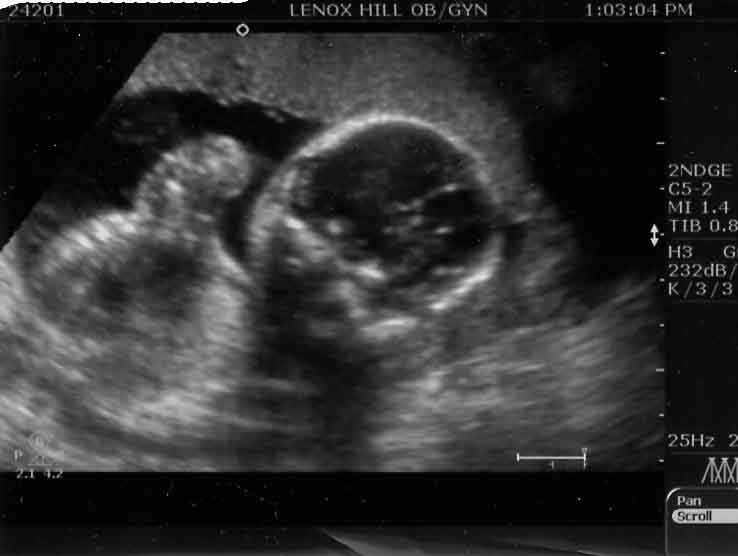

6 WEEKS.... Image Attachment(s):

12 WEEKS... Image Attachment(s):

20 WEEKS... Image Attachment(s):